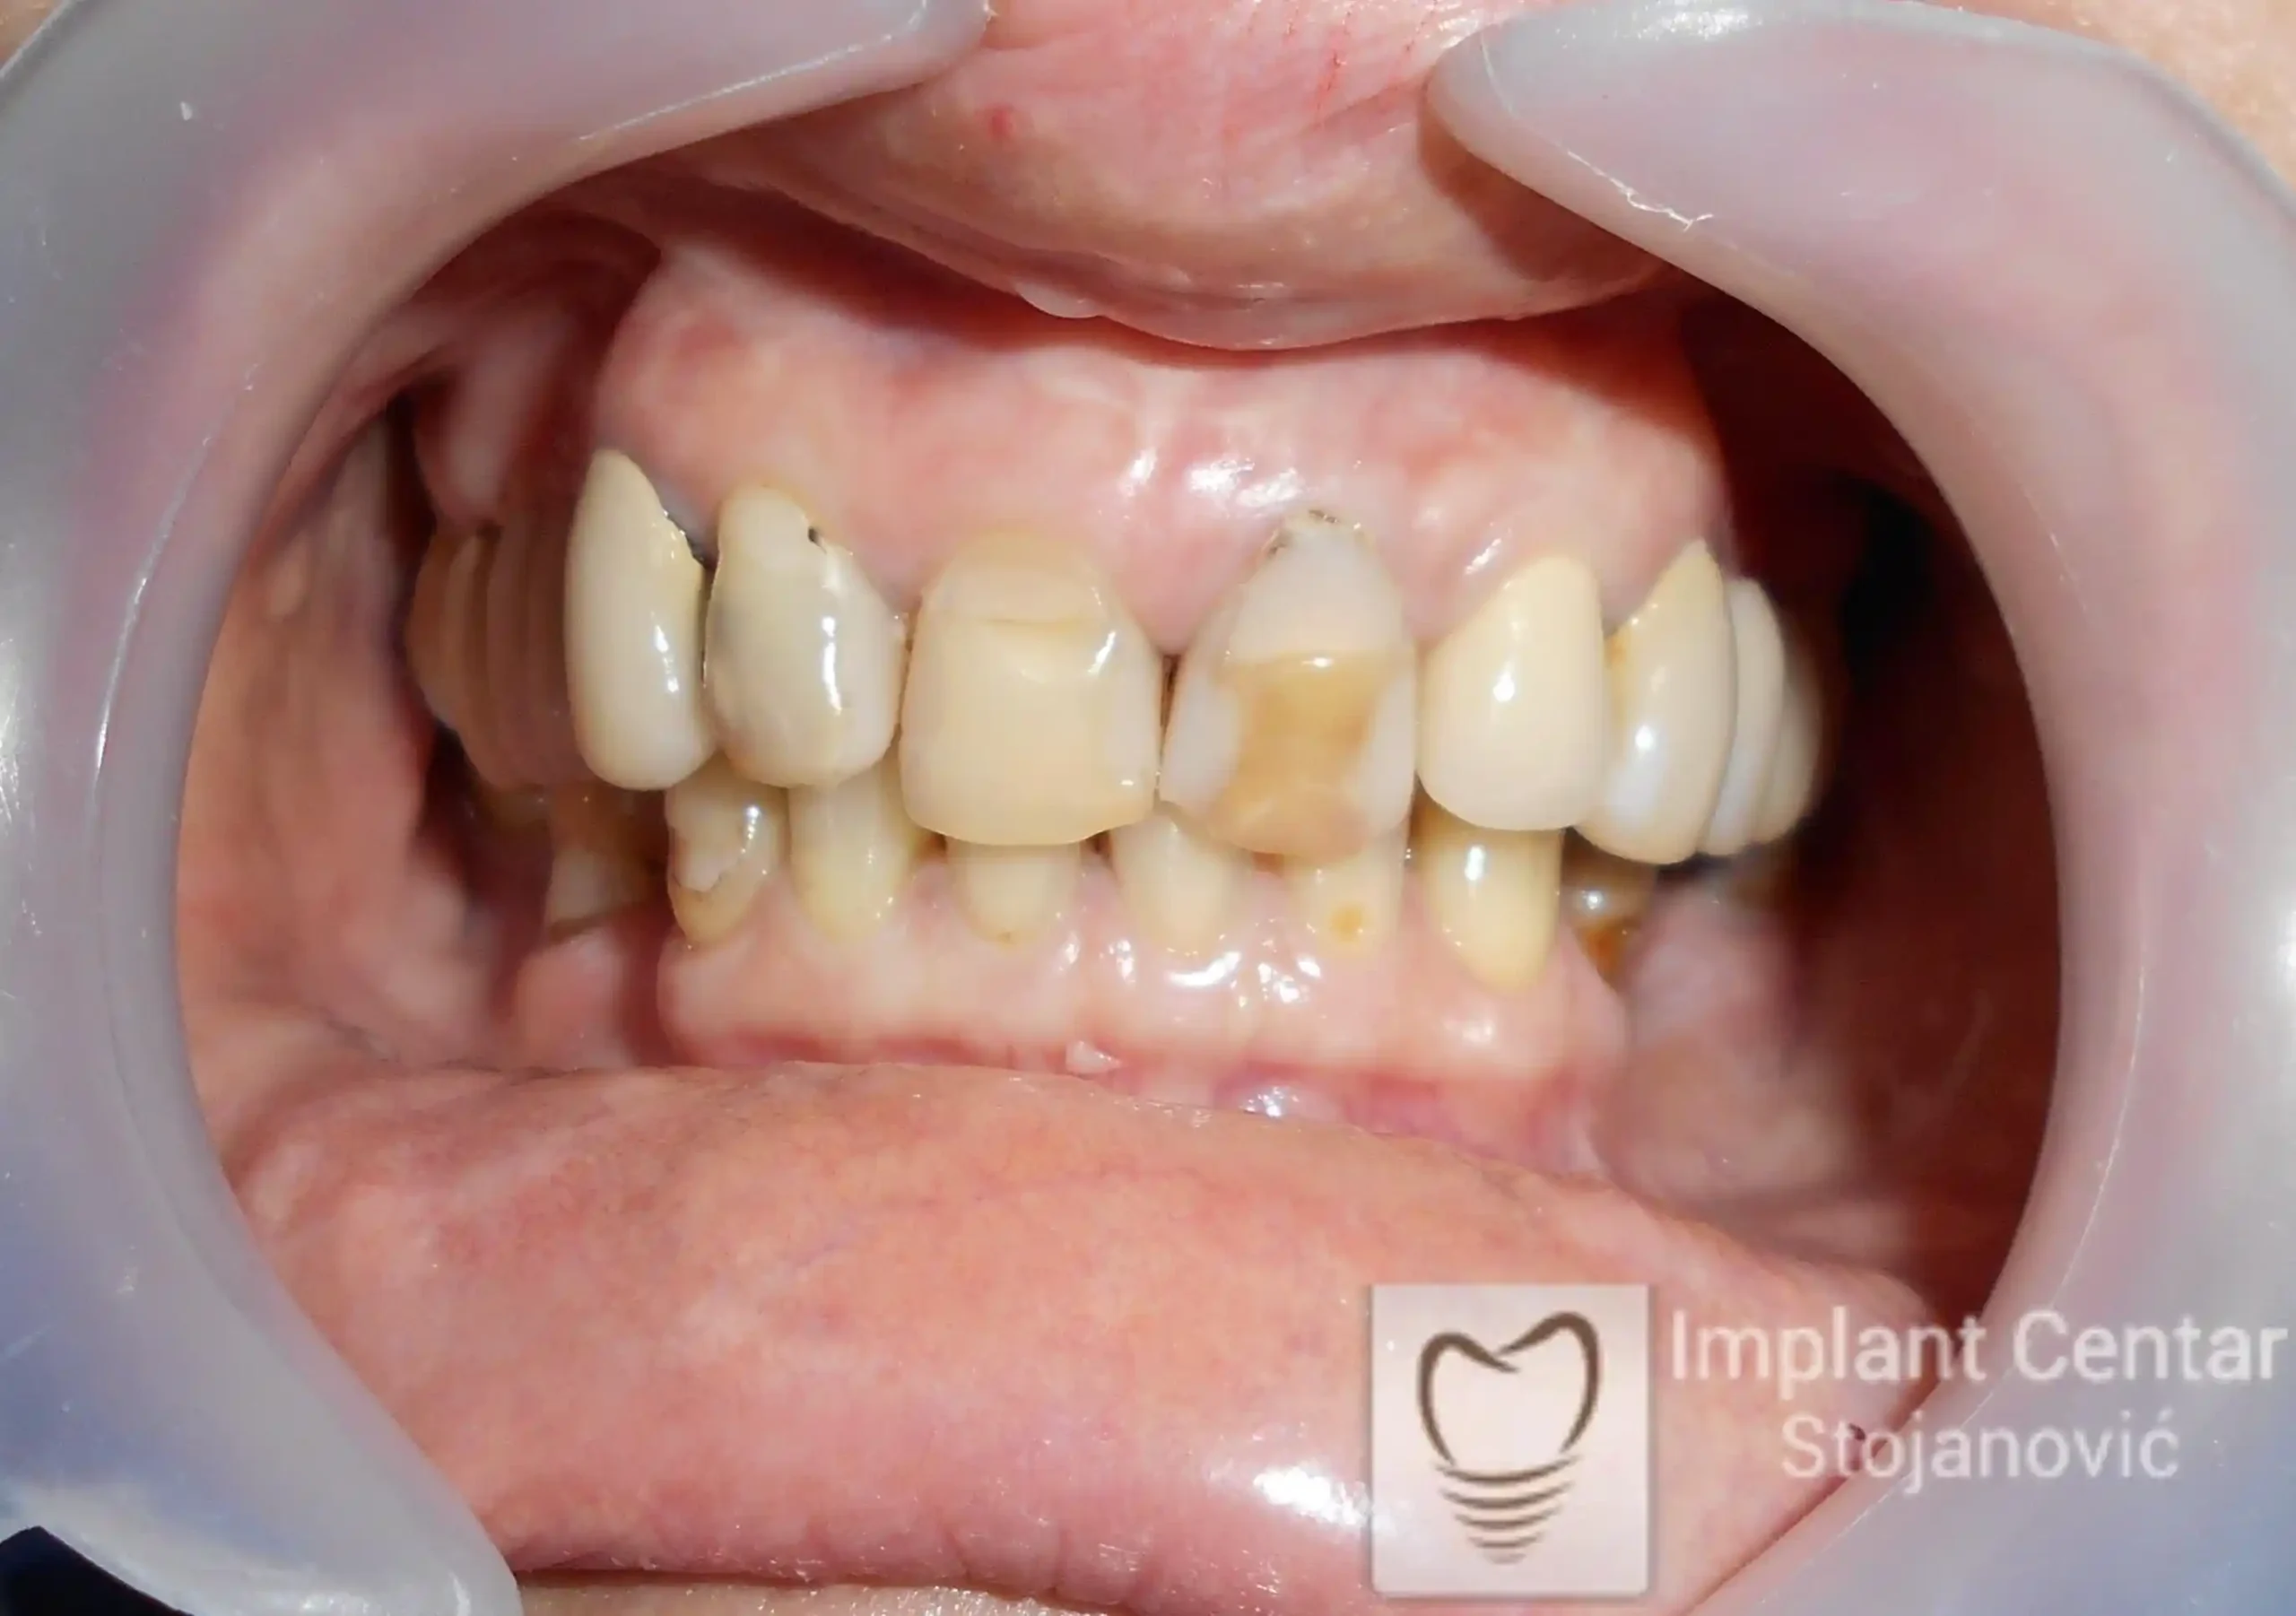

Na slikama 1 i 2 prikazan je klinički izgled pacijenta pre početka terapije. Nakon detaljnog kliničkog pregleda, analize radioloških snimaka, kao i razgovora sa pacijentom o njegovim željama i očekivanjima, izrađen je sveobuhvatan plan terapije. Terapija je podrazumevala vađenje preostalih zuba, ugradnju dentalnih implantata i izradu fiksnog protetskog rada na implantatima.

Tokom perioda osteointegracije, pacijent je bio zbrinut fiksnim privremenim krunicama na implantatima, čime su očuvani estetika i funkcija. Nakon završetka perioda integracije, izrađeni su definitivni cirkonijum-keramički mostovi (slika 6 i 7 ).

Pacijent je izuzetno zadovoljan postignutim rezultatom, jer su u potpunosti vraćeni prirodan izgled osmeha i puna oralna funkcija.